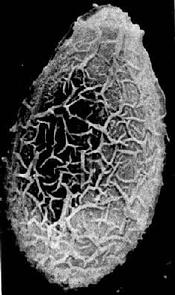

{{Hierarchy header}} 中华分支睾[[吸虫]][Clonorchis sinensis(Cobbold,1875)Looss,1907]简称[[华支睾吸虫]],又称肝吸虫。成虫[[寄生]]于肝的[[胆管]]内,可引起[[华支睾吸虫病]](clonorchiasis),又称[[肝吸虫病]]。本虫于1874年首次在加尔各答一华侨的[[肝管]]内发现。曾于湖北江陵县先后在西汉古尸和战国楚墓古尸查见此种虫卵,证明华支睾吸虫病在我国流行至少已有2300年以上的历史。 '''形态''' 成虫(图14-7)体形狭长,背腹扁平,前端尖细,后端略钝,体表无棘。虫体大小一般为10~25mm×3~5mm。口吸盘略大于[[腹吸盘]],后者位于虫体前端1/5处。[[消化道]]的前部有口、咽及短的[[食管]],然后分叉为两肠支伸至虫体后端。[[睾丸]]前后排列于虫体后端1/3处,呈分支状,从睾丸各发出一支输出管,约有虫体的中部会合为[[输精管]],向前逐渐膨大形成储[[精囊]]。储精囊接[[射精管开口]]于[[生殖]]腔。无[[阴茎]]和阴茎袋。[[卵巢]]边缘分叶,位于睾丸之前,[[受精囊]]在睾丸和卵巢之间,呈椭圆形。营氏管细长,弯曲,开口于虫体背面。[[卵黄腺]][[滤泡]]状,分布于虫体两侧,从腹吸盘向下延至受精囊水平。[[输卵管]]的远端为卵模,周围为梅氏腺。[[子宫]]从卵模开始盘绕而上,开口于腹吸盘前缘的生殖腔。 卵在近子宫前端已渐成熟,排出的卵呈黄褐色,内有成熟的毛蚴。卵甚小,平均为29×17µm,形状似[[芝麻]],一端较窄且有盖,盖周围的卵壳增厚、形成[[肩峰]],另一端有小[[疣状突起]](图14-7、14-8)。 '''生活史''' 成虫寄生于人或哺乳动物的胆管内。虫卵随[[胆汁]]进入消化道混于粪便排出,在水中被第一中间[[宿主]]淡水螺吞食后,在螺体消化道孵出毛蚴,穿过肠壁在螺体内发育,经历了胞蚴、[[雷蚴]]和[[尾蚴]]3个阶段。成熟的尾蚴从螺体逸出,遇到第二中间宿主淡水鱼类,则侵入鱼体内[[肌肉]]等组织发育为囊蚴。终宿主因食入含有囊蚴的鱼而被[[感染]]。囊蚴在[[十二指肠]]内[[脱囊]]。一般认为脱囊后的后尾蚴沿肝汁流动的逆方向移行,经[[胆总管]]至肝胆管, {{图片|gldogfau.jpg|华支睾吸虫成虫与虫卵}} 图14-7 华支睾吸虫成虫与虫卵 也可经血管或穿过肠壁经腹腔进入肝胆管内,通常在感染后1个月左右,发育为成虫(图14-9)。成虫在人体的寿命尚缺准确数据,一般认为有的可长达20~30年。 本虫对宿主的特异性要求并不严格。终宿主除肉食哺乳类动物外,在兔、豚鼠等食草动物也能正常发育。第一中间宿主淡水螺的种类很多,在我国至少有3科8种,常见的有纹沼螺(Parafossarulus striatulus),[[长角]]涵螺(Alocinma longicornis)和赤豆螺(傅氏豆螺(Bithynia fuchsianus)等。对第二中间宿主的选择更不强,国内已证实的淡水鱼宿主有12科39属68种。但从华支睾吸虫[[流行病学]]的角度看,养殖的淡水鲤科鱼类,如白鲩(草鱼)(Ctenopharyngodon idellus)、黑鲩([[青鱼]])(Mylopharyngodon aethiops)、鳊鱼(Hypophthalnichthys molitrix)、大头鱼(H.nobilis)、土鲮鱼(Labeocollaris及 L.kontius)[[鲤鱼]](Cyprinus carpio)等特别重要。野生小型鱼类如麦穗鱼(Pseudorosbora parva)[[感染率]]较高,尚有克氏[[鲦鱼]](Hemiculter kneri)等小鱼与传播儿童华支睾吸虫病有关。在台湾省日月潭地区,上述两种小鱼华支睾吸虫囊蚴的感染率甚至高达100%(Chen等.,1980)草鱼、[[鲫鱼]]的感染率也很高。除淡水鱼外,淡水虾如细足米虾(Caridna nilotica gracilipes)、巨掌沼虾(Macrobrachium superbum)等可有囊蚴寄生;甚至在某些特定条件下,尾蚴在螺体内也可发育为囊蚴。囊蚴寄生的部位,大部分在第二中间宿主的肌肉,但在鱼鳞和虾的甲壳表面也有发现(图14-9)。 {{图片|gldogggs.jpg|华支睾吸虫卵扫描电镜图}} 图14-8 华支睾吸虫卵扫描电镜图(许世锷供图) '''致病''' 本虫是厌氧性吸虫。在胆道中,成虫的营养和[[代谢]]还不很清楚。虫体[[组织化学]]研究及消化道内含物的分析结果显示消化道内有胆管[[上皮细胞]]、[[血液]]的各种成分和胆管分泌物等,但还不能认为这些物质是成虫的营养来源。虫体各组织中证实有碱性和[[酸性磷酸酶]],可能与[[多糖]]、[[脂类]]、[[碱性蛋白质]]的分布有关。[[乙酰胆碱]]脂酶主要分布于[[神经系统]]内。 {{图片|gldogebk.jpg|华支睾吸虫生活史}} 图14-9 华支睾吸虫生活史 华支睾吸虫病的危害性主要是患者的肝受损。虫体在胆道寄生时的代谢产物和机械刺激的结果。病变主要在肝的次级胆管。轻度感染或感染的初期病变并不明显。重度感染并经过相当长的时间后,胆管出现局限性的扩张,管壁增厚。大量的虫体可引起阻塞、胆汁滞留,如[[合并细菌感染]]可引起[[胆管炎]]和胆管[[肝炎]]。慢性感染可有大量的结缔[[纤维]]组织[[增生]],附近的肝实质可用明显[[萎缩]]。目前一般认为虫卵、死亡的虫体及其碎片、脱落的[[胆道感染]],破坏了胆道上皮的正常结构及功能,导致胆汗中[[细菌]]性β-[[葡萄糖醛酸]][[苷酶]]活性升高,其结果有利于难溶性[[胆红素]]钙的形成;胆道分泌[[糖蛋白]]的增多,并附着于虫卵表面作为[[结石]]核心,起支架和[[粘附]]剂作用,促进胆红素钙的沉积,最后导致色素类结石(即肝内多发性结石)的出现(郭日波等,1990)。此外,国内外一些资料不断提示华支睾吸虫感染与胆管[[上皮]]癌、[[肝细胞癌]]的发生有一定关系。 临床[[症状]]以[[疲乏]]、[[上腹]]不适、[[消化不良]]、[[腹痛]]、[[腹泻]]、肝区隐痛、[[头晕]]等较为常见,但许多感染者并无明显症状。常见的[[体征]]有肝肿大,[[脾肿大]]较少见,偶见发育欠佳类似[[侏儒症]]者。严重感染者在晚期可造成[[肝硬变]][[腹水]],甚至死亡。 '''实验诊断''' 病原检查 检获虫卵是确诊的主要依据。但因虫卵小,粪便直接[[涂片]]法易于漏检,故多采用各种集卵法(如水洗离心沉淀法,[[乙醚]]沉淀法等)和十二指肠[[引流]]胆汗进行离心沉淀检查。但该虫卵与异形吸虫卵相似,不易鉴别。 [[免疫诊断]] 皮内试验、[[间接血凝试验]]、[[对流免疫电泳]]试验、[[酶联免疫吸附试验]]、[[间接荧光抗体试验]]等都曾试用于华支睾[[吸虫病]]的辅助诊断,但检测病人结果出入较大,且与其它消化道[[寄生虫感染]](尤以[[吸虫类]]感染)有较明显的[[交叉反应]],不能用作确诊,现仅作为[[流行病学调查]]初筛之用。随着[[免疫学]]新技术的发展和应用,如能找到理想的诊断用[[抗原]],如[[纯化]]抗原、[[合成抗原]]等,当可解决上述问题。近年来,有学者曾试用夹心酶联免疫吸附试验等法检测循环抗原,其灵敏性及特异性优于循环[[抗体]]检测法。 '''流行''' 华支睾吸虫人体感染主要分布于远东,如中国、日本、朝鲜、越南和中南亚国家。我国除青海、宁夏、新疆、内蒙古、西藏等尚无报道外,已有24个省、市、自治区有不同程度流行,人群感染率在1%~30%之间。而[[保虫宿主]]动物感染的地区范围更广,感染率与感染度多比人体感染高,对人群的感染具有潜在的威胁。 华支睾吸虫对宿主的要求特异性不高,因此[[种群]]分布的[[生物]]限制因素较小。这可能是本虫能在广大地区存在的主要原因之一。 在自然环境中,本虫生活史过程中淡水的水量和水体保持的时间都必须满足[[中间宿主]]的孳生,而水温对幼虫期在外界的生存,感染宿主的机会以及中间宿主内的生存与发育都有直接的明显的影响。因此,一个地区的淡水资源和气候条件是造成本虫幼虫种群数量的季节性变化和地区性差别的主要原因之一,并可反映到终宿主的感染率和感染度以及一个地区的成虫种群数量上。 实验证明以尾蚴感染白[[鲩鱼]]苗,在10℃以下时尾蚴完全不能侵入鱼体,15℃时可有少数侵入,20~30℃明显增多,25℃最多。从尾蚴感染到囊蚴成熟的时间,在水温15℃时,约在感染后的60天左右,25℃时只需30~40天。囊蚴在鱼体的季节消长。在台北,麦穗鱼夏季的感染率为100%,每条鱼平均感染418个囊蚴,秋季为96.6%,感染度为309;冬季为80%,感染度为96;春季为83.3%,感染度为227(Huang and Khaw,1964)。在山东,鱼类的囊蚴感染率从9月逐渐上升,11月份到达顶峰。在东北铁岭县,麦穗鱼和爬虎鱼囊蚴感染率以8、9两月最高,10月以后逐渐降低,次年1月最低。 华支睾吸虫病在一个地区流行的关键因素是当地人群有吃生的或未煮熟的鱼肉的习惯。由于各地吃鱼方法不同,感染的方式和对象也不一样。在广东主要通过吃“鱼生”“鱼生粥”或烫鱼片而感染,男性成年人的感染率较高;在东北地区,特别是朝鲜族居民主要是通过生鱼佐酒吃而感染,亦以男性成年人较多;此外一些地区,如北京、山东、河北、四川等地多以从河沟、池溏捉的鱼烧吃或烤吃而感染,主要为20岁以下的青少年和儿童;抓鱼后不洗手或用口叨鱼也是感染的原因;使用切过生鱼的刀及砧板切熟食物品,用盛过生鱼的器皿盛熟食物品也有使人感染的可能。 实验证明,在厚度约1mm的鱼肉片内含有的囊蚴,在90℃的热水中,一秒钟即能死亡,75℃时3秒内死亡,70℃及60℃时分别在6及15秒内全部死亡。囊蚴在醋(含[[醋酸]]浓度3.36%)中,可活2个小时;在酱油中(含NaCl 19.3%)5小时全部死亡。但在烧、烤、烫或蒸全鱼时,可因温度不够、时间不足或鱼肉过厚等原因,未能杀死全部囊蚴。 我国食用的鲤科鱼类和一些小杂鱼和豆螺、沼螺、涵[[螺生]]活在同一水域中,若人或动物粪便污染水域,而当地又有吃生的或半生的鱼虾习惯,本病就可能在人群中流行。如广东的珠江三角洲鱼类养殖业发达,以往长期以来人粪又常作为养鱼的[[饲料]]以及居民吃鱼习惯等是该病在当地流行的原因。 '''防治原则''' 大力做好卫生宣传教育工作,提高群众对本病[[传播途径]]的认识,自觉不吃生的或不熟的鱼虾。改进烹调方法和改变饮食习惯,注意分开使用切生、熟食物的菜刀、砧板及器皿。也不用生鱼喂猫、犬。 积极治疗病人和感染者,是保护人民健康、减少[[传染源]]的积极措施。治疗药物目前[[吡喹酮]](Praziquantel)为首选药。 合理处理粪便,改变养鱼的习惯,都是预防华支睾吸虫病传播的重要措施。 此外,结合生产的需要,清理塘泥、[[消毒]]鱼塘,对杀灭螺类有一定效果。 ==参看== *[[华支睾吸虫]] {{Hierarchy footer}} {{人体寄生虫学图书专题}}